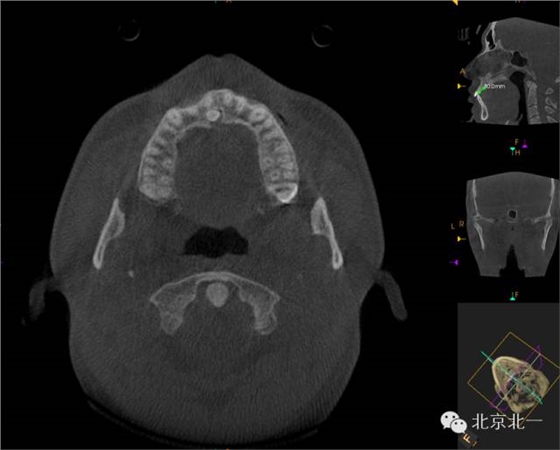

CBCT顯示埋伏多生牙位于腭側高位,接近切牙管開口位置。

CBCT矢狀位顯示多生牙倒置阻生,位于鼻腭神經(jīng)管口

CBCT冠狀位顯示多生牙位于鼻腭神經(jīng)管

三維重建效果圖